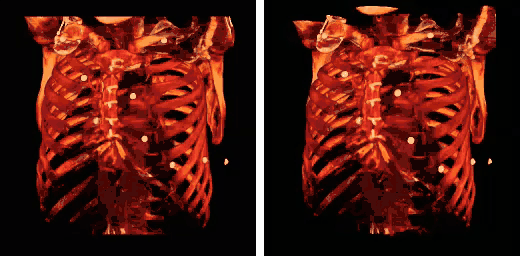

Human rib cage - CT scan (parallel projection (left) and perspective projection (right))